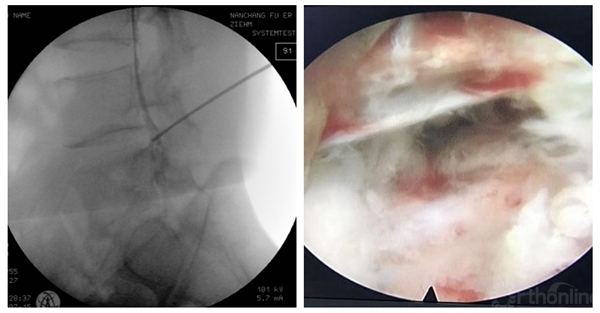

术前造影显示后纵韧带完整性,术中保护后纵韧带

脊柱内镜日间手术需进一步提高穿刺的精准性,避免反复穿刺。

靶向穿刺